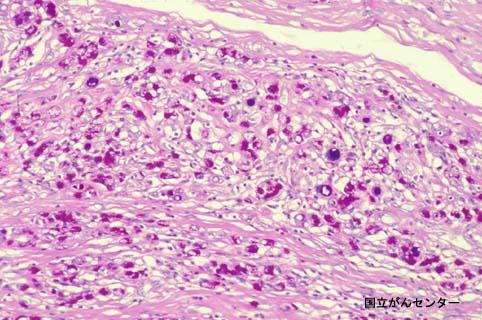

질환(병리주체)의 분류 악성 상피성종양/인환세포암

부위(장기별) 위(부위)/전정

검사방법 마이크로

종양의 육안분류 0형(표재형)/IIc형(IIc)

종양의 최대경(밀리미터) 20~24

종양의 심달도 sm